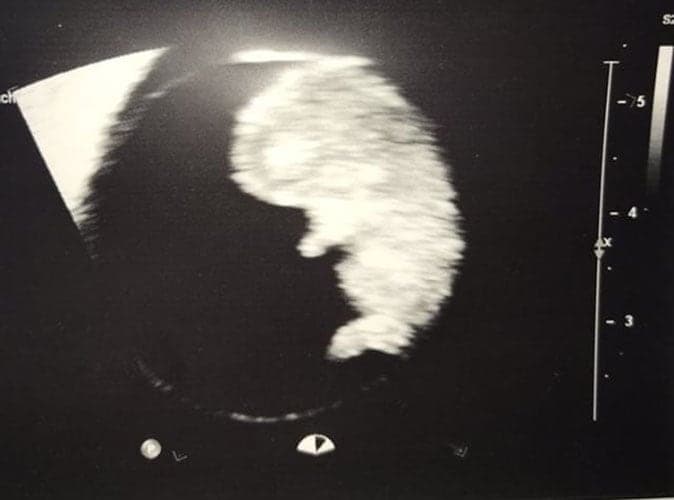

Ultraschallbilder aus dem 3. Trimester (29. bis 40. SSW)

Im dritten Trimester der Schwangerschaft ist das Baby so groß, dass es nicht mehr komplett auf ein Ultraschallbild passt. Nun kann man wunderbare 3D-Ultraschalle des Gesichts machen. In diesem Semester nehmen die Babys nochmal rasant zu und wer Glück hat, kann auf seinem Ultraschall schon erste Gesichtszüge erkennen.